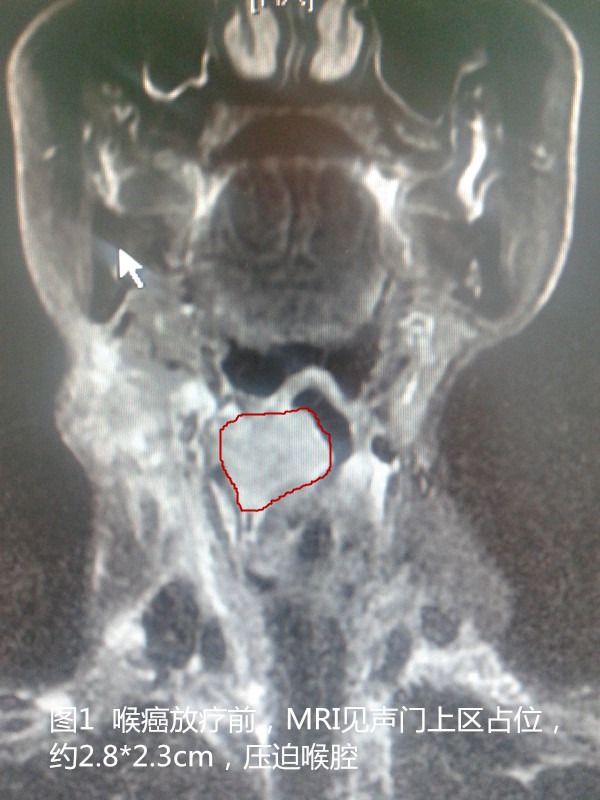

2014年3月,75岁的施大爷无意中摸到颈部长了一个小肿块,刚开始老大爷也没在意,长个小疙瘩,不碍吃也不碍喝的。谁知,小疙瘩越来越大,这下一家可慌了神。一家人把施大爷带到了人民医院做检查,最终诊断为喉癌淋巴结转移(见下图1)。

后来患者找到了沭阳县人民医院肿瘤科专家姚型锋。姚主任介绍:喉癌是头颈部常见的恶性肿瘤之一,近年来喉癌的发病率有增多的趋势。喉癌常见临床症状有:声音嘶哑、咽喉部异物感、痰中带血、饮水呛咳等。自沭阳县人民医院开展三维适形、调强放疗以来,已治疗头颈部恶性肿瘤一百余例。处方剂量可达66-70Gy/33-35F。治疗效果确切,肿瘤明显消退,痛苦小,声音嘶哑、咽喉部不适能得到明显好转。同时姚主任提醒大家:凡是有不明原因的声音嘶哑、咽喉部异物感、咽下疼痛及痰中带血的病人,尤其是年龄超过40岁、嗜烟酒者均应做必要的检查。下图为上文介绍病例影像学资料前后比较,治疗前后MRI显示,喉腔肿瘤明显缩小,调强放疗治疗效果好。